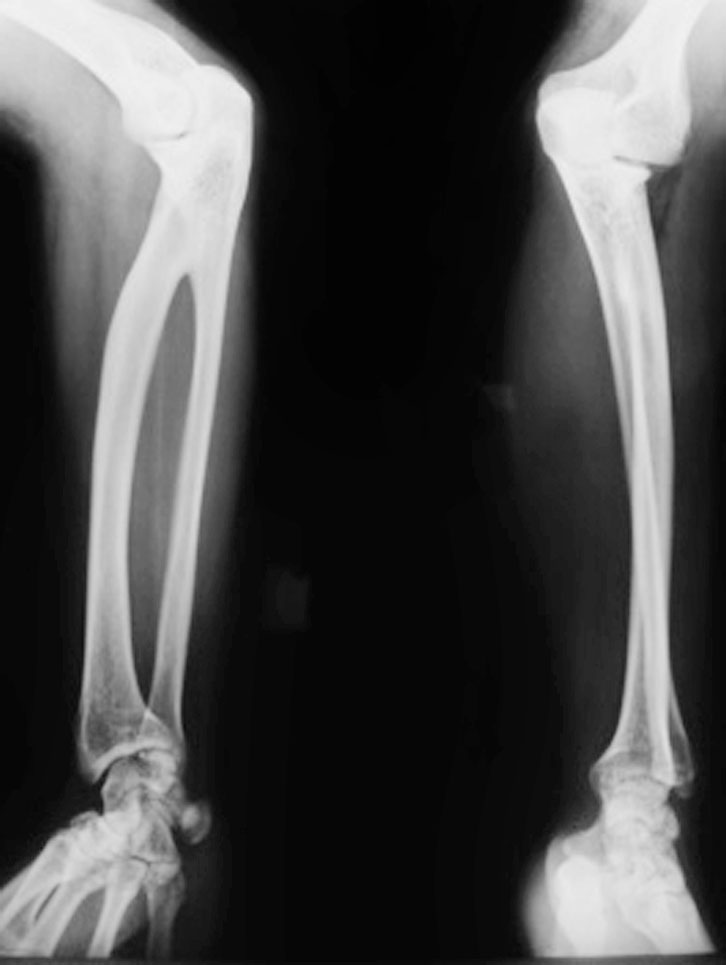

图1-2-13 先天性多发关节挛缩症病例

A.先天性多发关节挛缩症,累及双手关节;B.同时合并有肩关节、肘关节挛缩;C.该病例还合并有膝、踝关节挛缩